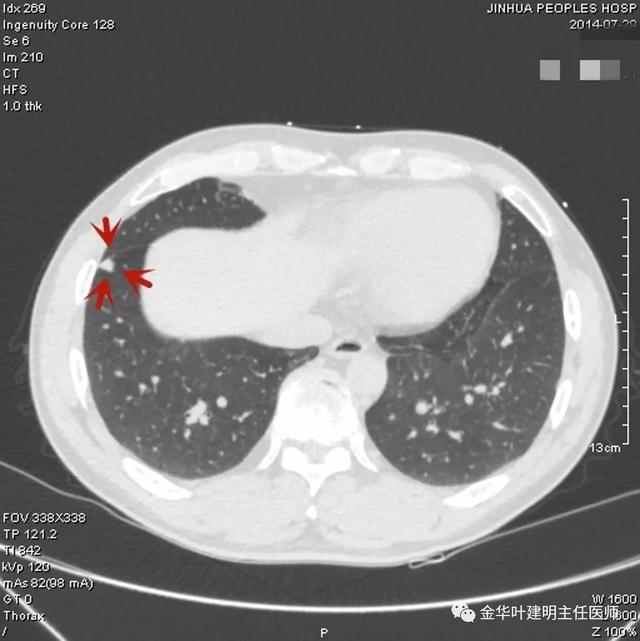

上图示慢性炎结节。我们见其桔色箭头示长毛刺征,绿色箭头示有血管贴边,但进出病灶的血管粗细相对没有什么改变(说明没有被病灶窃取多少血供),整体病灶边缘偏模糊。